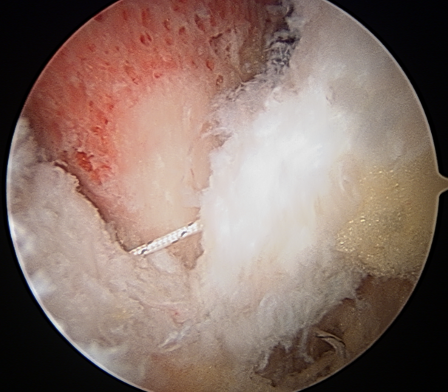

Labral debridement

- for degenerative / irreparable / ossified labrum / failed labral repair